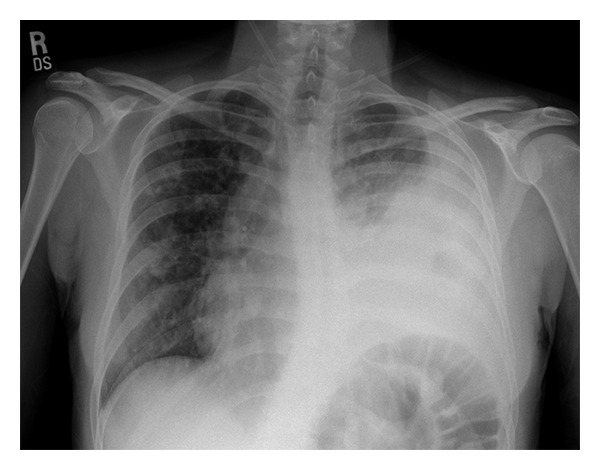

Input 3: What is seen in the X-ray and what should be done? Image:

- Visual Med-Alpaca: Bilateral infiltrates and bilateral pleural effusion seen in a chest x-ray may indicate a respiratory infection or other respiratory conditions such as pneumonia pulmonary edema, or pleural effusion, it is important to consult a medical professional for a proper diagnosis and treatment plan.

OTHER METHODS

- VQA Medical Model: the decubitus

- Automatic Radiology Report Generation (Image-only): near complete opacification of the left hemi thorax with only a small amount of residual aerated lung in the left upper lobe .

- ChatGPT (GPT-3.5-Turbo) + Automatic Radiology Report Generation (Image-only): Opacification of the lung on an X-ray indicates that there is an abnormality in the lung tissue. In this case, the near-complete opacification of the left hemithorax with only a small amount of residual aerated lung in the left upper lobe suggests that there is likely a significant pathology present in the left lung. Possible causes of this finding include pneumonia, lung abscess, tumor or mass, or pleural effusion (fluid accumulation around the lung). It is important to determine the underlying cause of this finding as soon as possible. A follow-up diagnostic workup may include a CT scan of the chest, sputum culture, bronchoscopy, and/or a biopsy of any suspicious areas in the lung. The appropriate treatment will depend on the underlying cause, but it may include antibiotics, drainage of any fluid collections, or surgery to remove any masses or tumors. Prompt evaluation and treatment are necessary to prevent complications and improve outcomes.